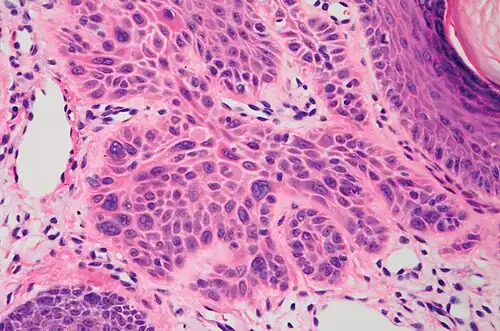

Invasive disease

In invasive cSCC, tumor cells infiltrate through the basement membrane. The infiltrate can be somewhat difficult to detect in the early stages of invasion: however, additional indicators such as full-thickness epidermal atypia and the involvement of hair follicles can be used to facilitate the diagnosis. Later stages of invasion are characterized by the formation of nests of atypical tumor cells in the dermis, often with a corresponding inflammatory infiltrate.[12]

Superficially invasive cutaneous squamous-cell carcinoma. These lesions often do not show the marked pleomorphism and atypical nuclei of cSCC in situ, but manifest early keratinocyte invasion of the dermis.[12] -

High magnification demonstrates the pleomorphism of the invading keratinocytes[12] -

Invasive nests with characteristic large celled centers. Ulceration (at left) is common in invasive cSCC.